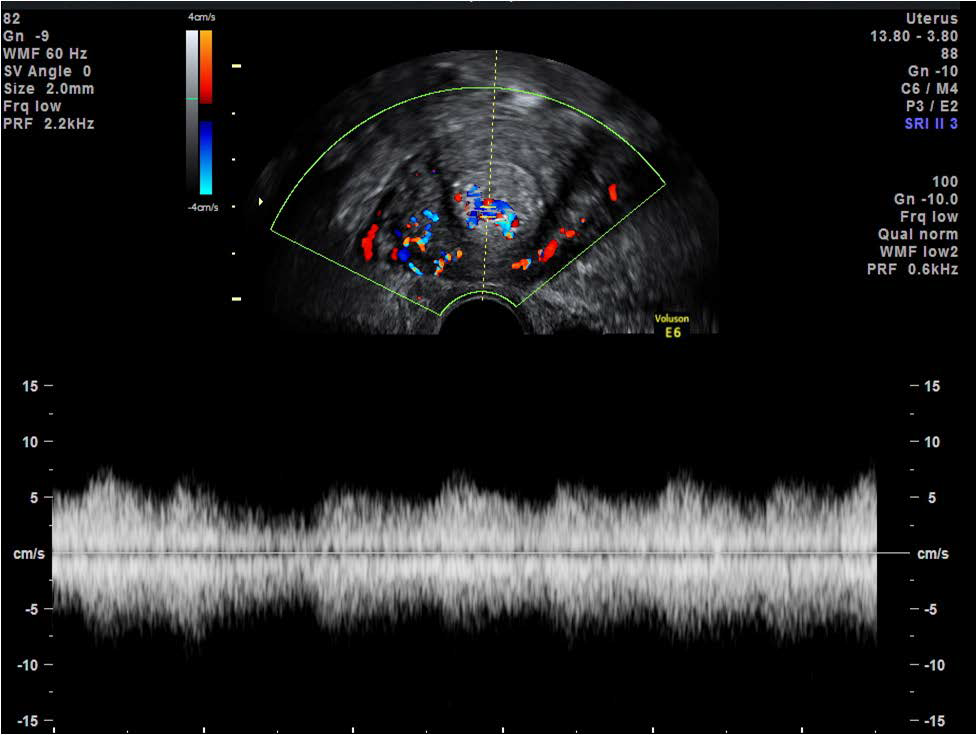

Figure 9: Application of colour Doppler demonstrates trophoblastic blood flow to the region of the echogenic mass in the transverse plane on transvaginal scan (as seen in Figure 8) aiding diagnosis of retained products of conception.